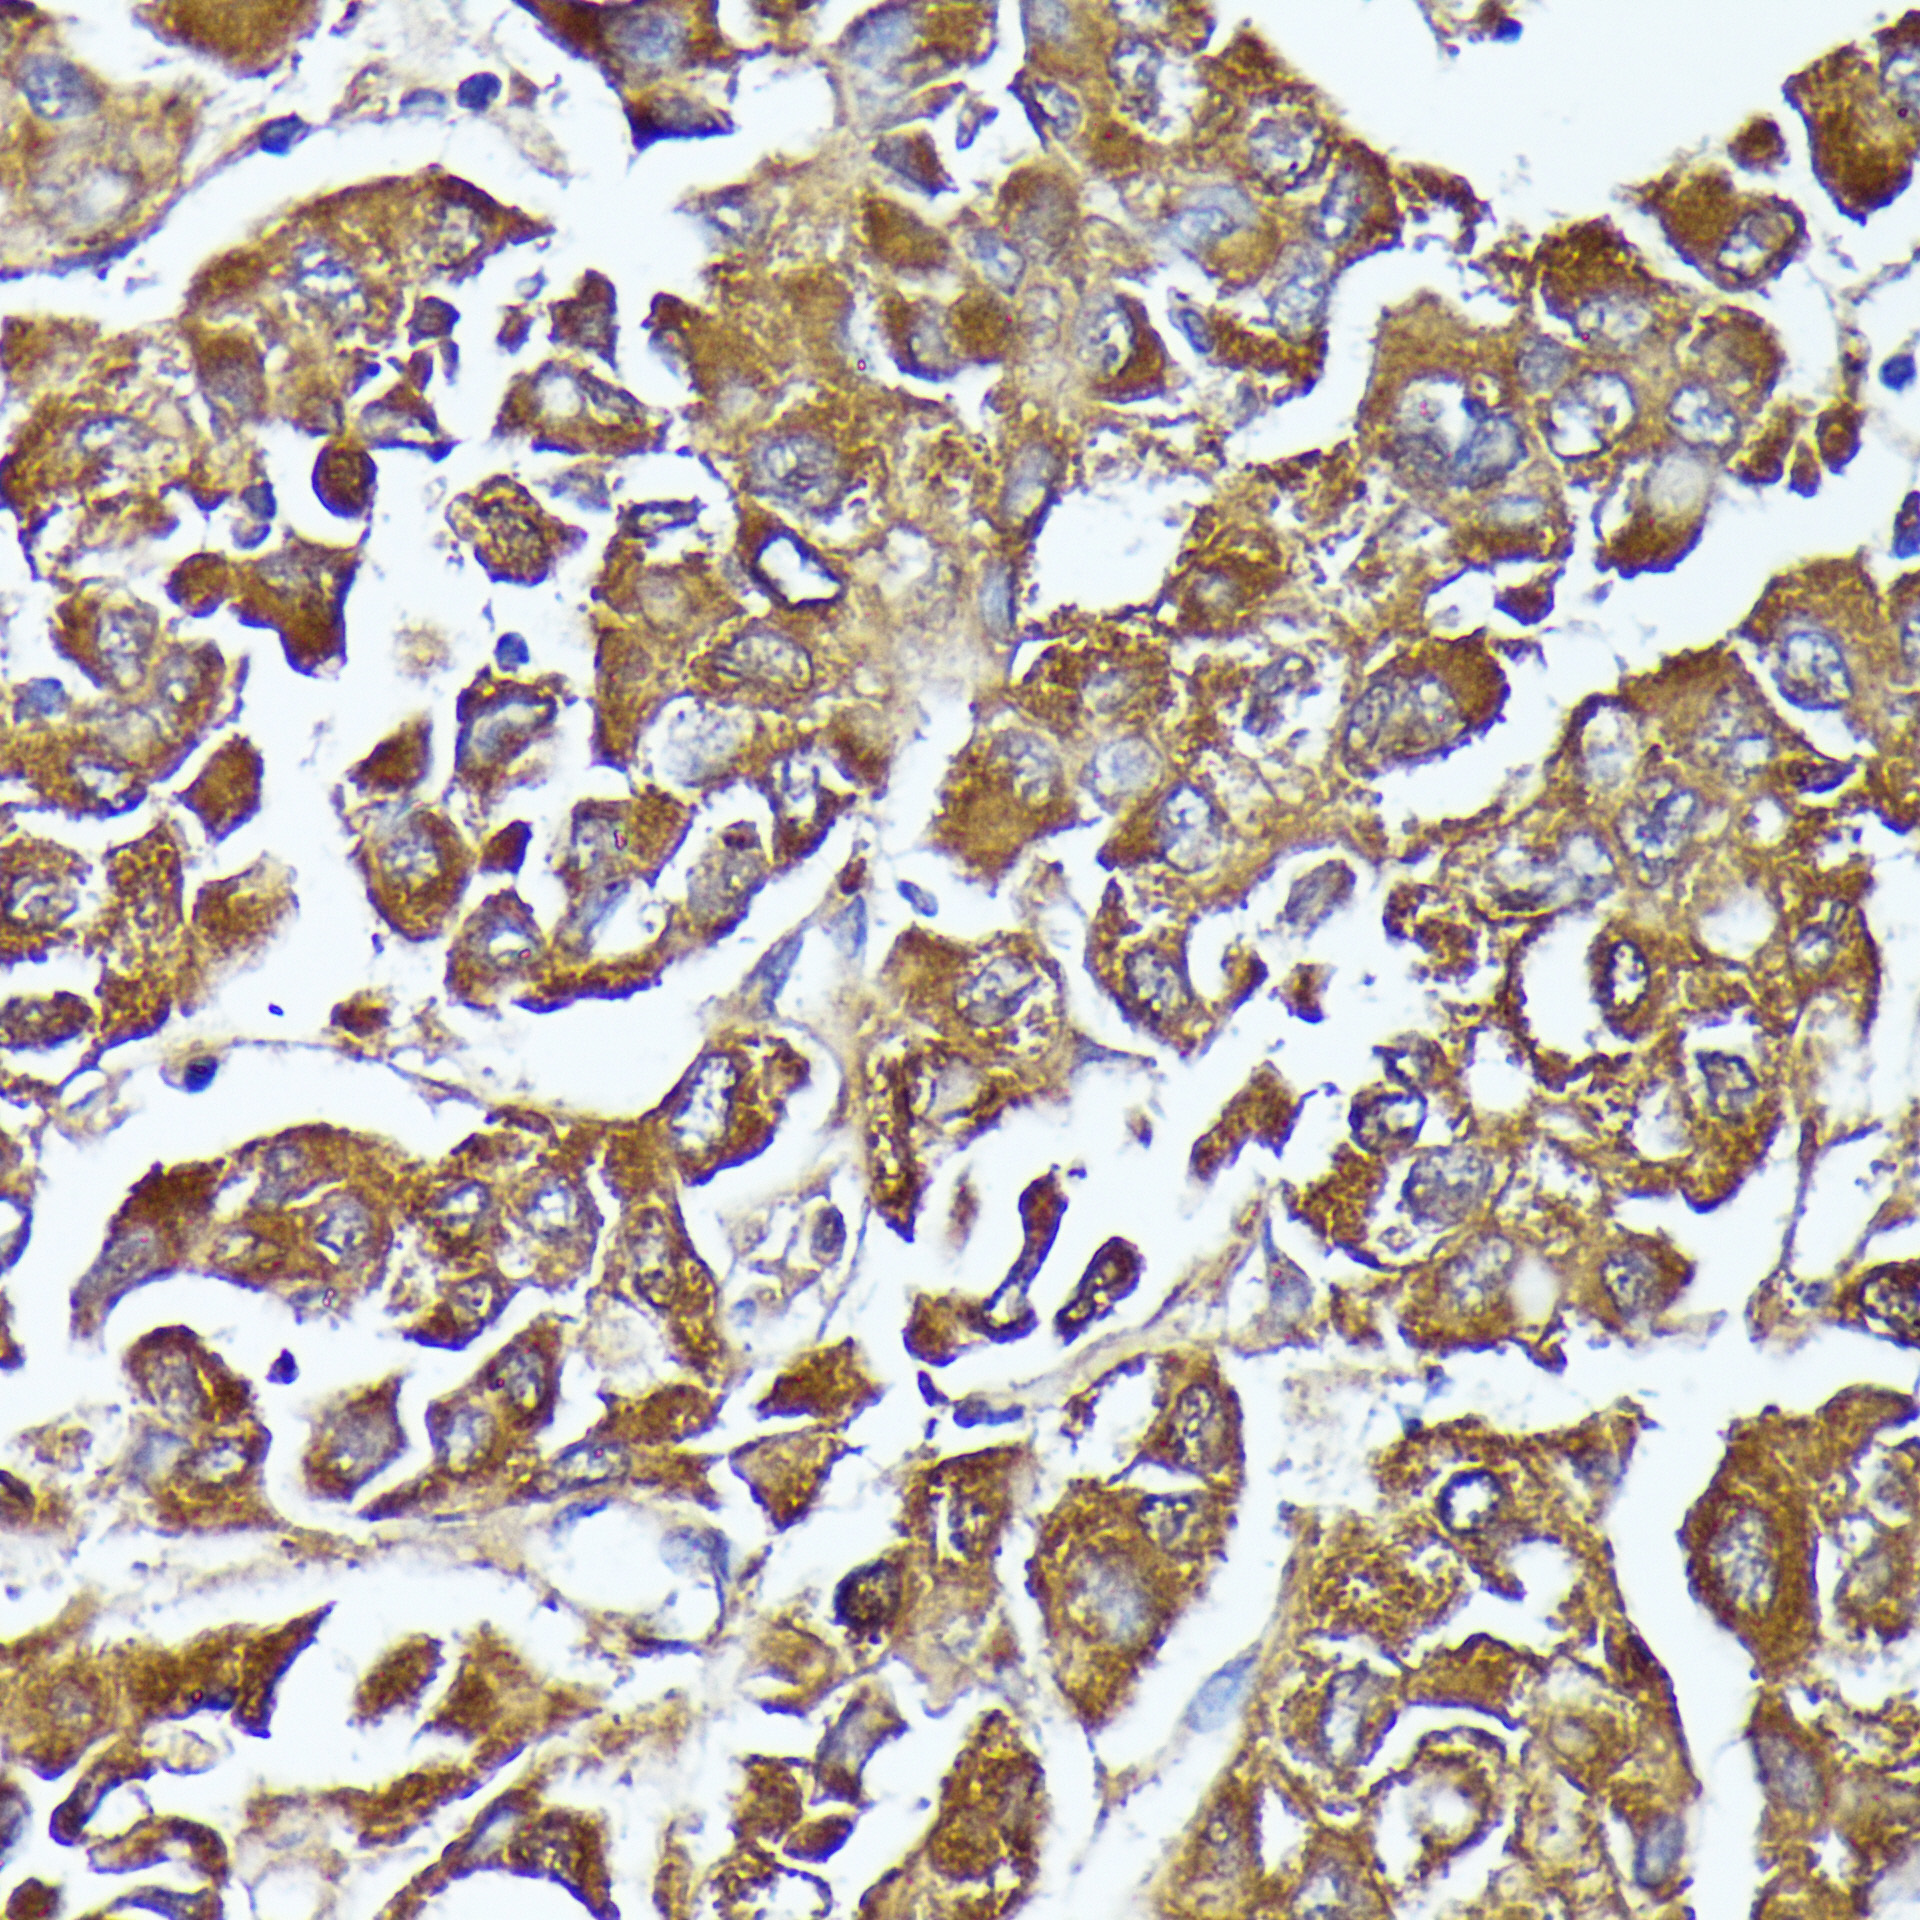

Immunohistochemistry of paraffin-embedded rat liver using AKR1C2 Rabbit pAb.

Immunohistochemistry of paraffin-embedded human liver cancer using AKR1C2 Rabbit pAb.

Immunohistochemistry of paraffin-embedded human Colon cancer using AKR1C2 Rabbit pAb.

Immunohistochemistry of paraffin-embedded mouse liver using AKR1C2 Rabbit pAb.